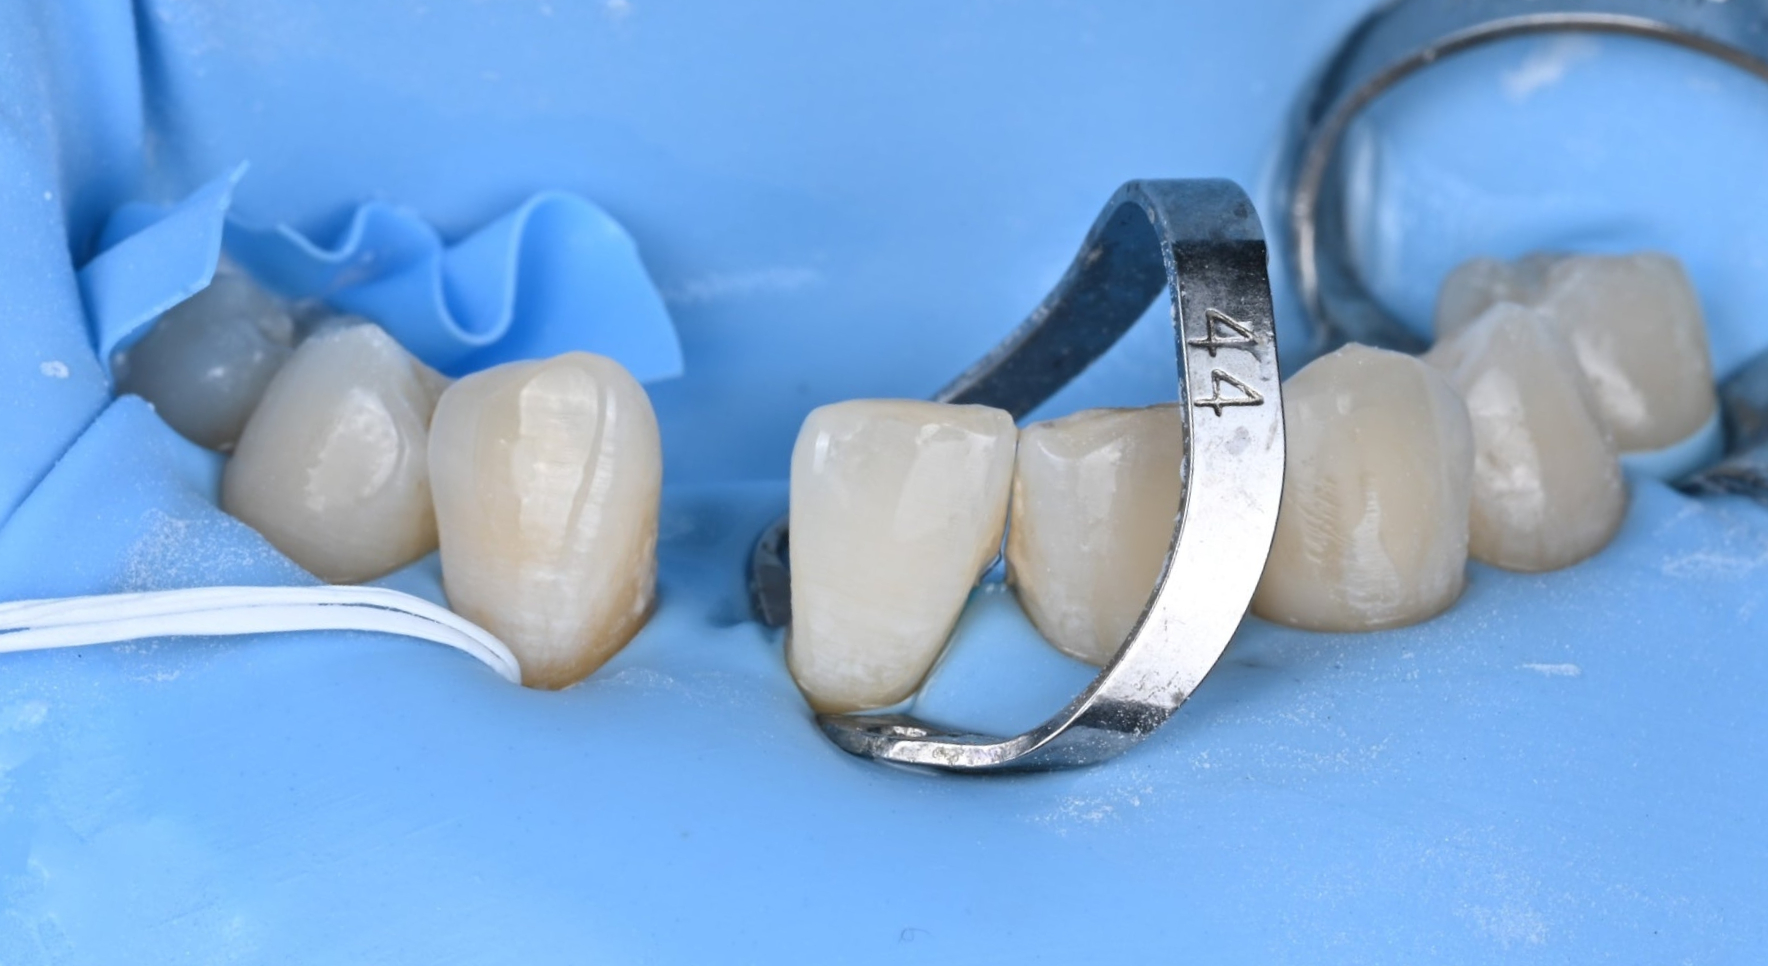

26.04.02 메릴랜드 브릿지 접착 준비